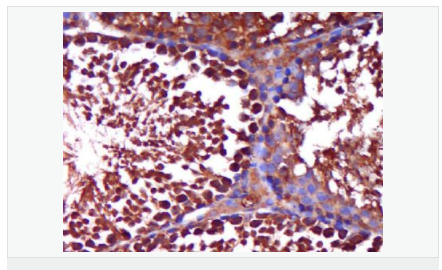

| 產(chǎn)品應(yīng)用 | WB=1:500-2000 ELISA=1:5000-10000 IHC-P=1:100-500 IHC-F=1:100-500 Flow-Cyt=1ug/Test IF=1:100-500 (石蠟切片需做抗原修復(fù)) not yet tested in other applications. optimal dilutions/concentrations should be determined by the end user. |

| 細(xì)胞定位 | 細(xì)胞核 細(xì)胞漿 |

| 產(chǎn)品介紹 | The androgen receptor gene is more than 90 kb long and codes for a protein that has 3 major functional domains: the N-terminal domain, DNA-binding domain, and androgen-binding domain. The protein functions as a steroid-hormone activated transcription factor. Upon binding the hormone ligand, the receptor dissociates from accessory proteins, translocates into the nucleus, dimerizes, and then stimulates transcription of androgen responsive genes. This gene contains 2 polymorphic trinucleotide repeat segments that encode polyglutamine and polyglycine tracts in the N-terminal transactivation domain of its protein. Expansion of the polyglutamine tract causes spinal bulbar muscular atrophy (Kennedy disease). Mutations in this gene are also associated with complete androgen insensitivity (CAIS). Two alternatively spliced variants encoding distinct isoforms have been described. [provided by RefSeq, Jul 2008] Function: Steroid hormone receptors are ligand-activated transcription factors that regulate eukaryotic gene expression and affect cellular proliferation and differentiation in target tissues. Transcription factor activity is modulated by bound coactivator and corepressor proteins. Transcription activation is down-regulated by NR0B2. Activated, but not phosphorylated, by HIPK3 and ZIPK/DAPK3. [ENZYME REGULATION] AIM-100 (4-amino-5,6-biaryl-furo[2,3-d]pyrimidine) suppresses TNK2-mediated phosphorylation at Tyr-267. Inhibits the binding of the Tyr-267 phosphorylated form to androgen-responsive enhancers (AREs) and its transcriptional activity. Subunit: Binds DNA as a homodimer. Part of a ternary complex containing AR, EFCAB6/DJBP and PARK7. Interacts with HIPK3 and NR0B2 in the presence of androgen. The ligand binding domain interacts with KAT7/HBO1 in the presence of dihydrotestosterone. Interacts with EFCAB6/DJBP, PELP1, PQBP1, RANBP9, RBAK, SPDEF, SRA1, TGFB1I1, ZNF318 and RREB1. Interacts with ZMIZ1/ZIMP10 and ZMIZ2/ZMIP7 which both enhance its transactivation activity. Interacts with SLC30A9 and RAD54L2/ARIP4. Interacts via the ligand-binding domain with LXXLL and FXXLF motifs from NCOA1, NCOA2, NCOA3, NCOA4 and MAGEA11. The AR N-terminal poly-Gln region binds Ran resulting in enhancement of AR-mediated transactivation. Ran-binding decreases as the poly-Gln length increases. Interacts with HIP1 (via coiled coil domain). Interacts (via ligand-binding domain) with TRIM68. Interacts with TNK2. Interacts with USP26. Interacts with RNF6. Interacts (regulated by RNF6 probably through polyubiquitination) with RNF14; regulates AR transcriptional activity. Interacts with PRMT2 and TRIM24. Interacts with GNB2L1/RACK1. Interacts with RANBP10; this interaction enhances dihydrotestosterone-induced AR transcriptional activity. Interacts with PRPF6 in a hormone-independent way; this interaction enhances dihydrotestosterone-induced AR transcriptional activity. Interacts with STK4/MST1. Interacts with ZIPK/DAPK3. Interacts with LPXN. Interacts with MAK. Part of a complex containing AR, MAK and NCOA3. Subcellular Location: Nucleus. Cytoplasm. Note=Predominantly cytoplasmic in unligated form but translocates to the nucleus upon ligand-binding. Can also translocate to the nucleus in unligated form in the presence of GNB2L1. Tissue Specificity: Isoform 2 is mainly expressed in heart and skeletal muscle. Post-translational modifications: Sumoylated on Lys-386 (major) and Lys-520. Ubiquitinated. Deubiquitinated by USP26. 'Lys-6' and 'Lys-27'-linked polyubiquitination by RNF6 modulates AR transcriptional activity and specificity. Phosphorylated in prostate cancer cells in response to several growth factors including EGF. Phosphorylation is induced by c-Src kinase (CSK). Tyr-534 is one of the major phosphorylation sites and an increase in phosphorylation and Src kinase activity is associated with prostate cancer progression. Phosphorylation by TNK2 enhances the DNA-binding and transcriptional activity and may be responsible for androgen-independent progression of prostate cancer. Phosphorylation at Ser-81 by CDK9 regulates AR promoter selectivity and cell growth. Phosphorylation by PAK6 leads to AR-mediated transcription inhibition. Palmitoylated by ZDHHC7 and ZDHHC21. Palmitoylation is required for plasma membrane targeting and for rapid intracellular signaling via ERK and AKT kinases and cAMP generation. DISEASE: Defects in AR are the cause of androgen insensitivity syndrome (AIS) [MIM:300068]; previously known as testicular feminization syndrome (TFM). AIS is an X-linked recessive form of pseudohermaphroditism due end-organ resistance to androgen. Affected males have female external genitalia, female breast development, blind vagina, absent uterus and female adnexa, and abdominal or inguinal testes, despite a normal 46,XY karyotype. Defects in AR are the cause of spinal and bulbar muscular atrophy X-linked type 1 (SMAX1) [MIM:313200]; also known as Kennedy disease. SMAX1 is an X-linked recessive form of spinal muscular atrophy. Spinal muscular atrophy refers to a group of neuromuscular disorders characterized by degeneration of the anterior horn cells of the spinal cord, leading to symmetrical muscle weakness and atrophy. SMAX1 occurs only in men. Age at onset is usually in the third to fifth decade of life, but earlier involvement has been reported. It is characterized by slowly progressive limb and bulbar muscle weakness with fasciculations, muscle atrophy, and gynecomastia. The disorder is clinically similar to classic forms of autosomal spinal muscular atrophy. Note=Caused by trinucleotide CAG repeat expansion. In SMAX1 patients the number of Gln ranges from 38 to 62. Longer expansions result in earlier onset and more severe clinical manifestations of the disease. Note=Defects in AR may play a role in metastatic prostate cancer. The mutated receptor stimulates prostate growth and metastases development despite of androgen ablation. This treatment can reduce primary and metastatic lesions probably by inducing apoptosis of tumor cells when they express the wild-type receptor. Defects in AR are the cause of androgen insensitivity syndrome partial (PAIS) [MIM:312300]; also known as Reifenstein syndrome. PAIS is characterized by hypospadias, hypogonadism, gynecomastia, genital ambiguity, normal XY karyotype, and a pedigree pattern consistent with X-linked recessive inheritance. Some patients present azoospermia or severe oligospermia without other clinical manifestations. Similarity: Belongs to the nuclear hormone receptor family. NR3 subfamily. Contains 1 nuclear receptor DNA-binding domain. SWISS: P10275 Gene ID: 367 Database links: Entrez Gene: 367 Human Entrez Gene: 11835 Mouse Omim: 313700 Human SwissProt: P10275 Human SwissProt: P19091 Mouse Unigene: 496240 Human Unigene: 39005 Mouse Unigene: 394224 Mouse Unigene: 439657 Mouse Unigene: 9813 Rat Important Note: This product as supplied is intended for research use only, not for use in human, therapeutic or diagnostic applications. AR是一個由917個氨基酸組成的蛋白質(zhì),位于雄激素靶組織細(xì)胞中或細(xì)胞表面上的特異分子部位或結(jié)構(gòu)。 AR在前列腺癌中起著重要的作用,研究表明AR的表達(dá)與組織分型形成一定的相關(guān)性 ,AR在高分化的腫瘤中表達(dá)較多,而在低分化的腫瘤中表達(dá)較少。用于前列腺癌的檢測,指導(dǎo)臨床治療,目前可用于乳腺癌、食道癌等各項腫瘤的研究。 |